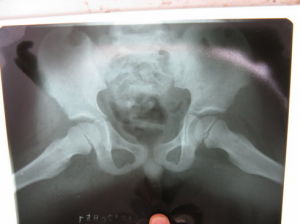

(四)X線檢查

X線片主要表現為髖關節骨性結構無異常,有時可見關節囊陰影膨隆。關節腔積液嚴重時可見股骨頭向外側移位,關節間隙增寬。